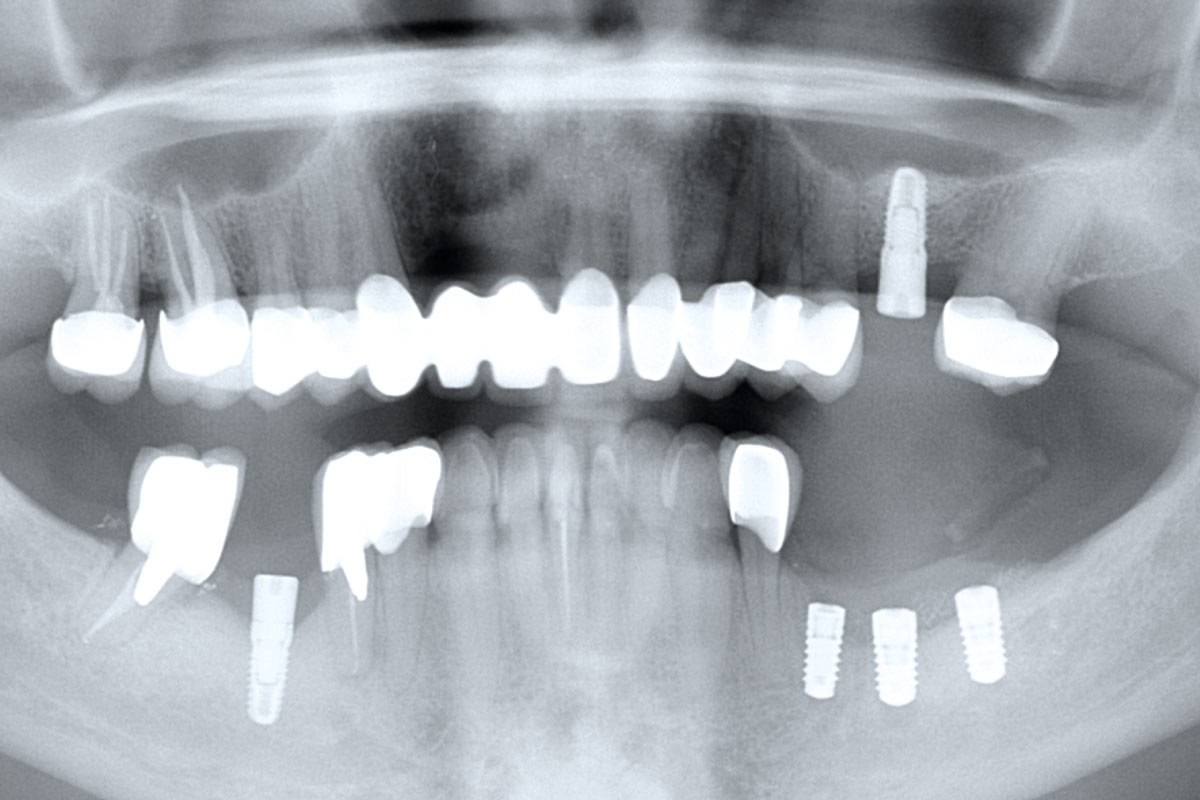

09/12 - Radiographic control after implantation

Ridge augmentation in the mandible with maxgraft® bonebuilder in a free-end situation - Dr. Dr. Dr. O. Blume